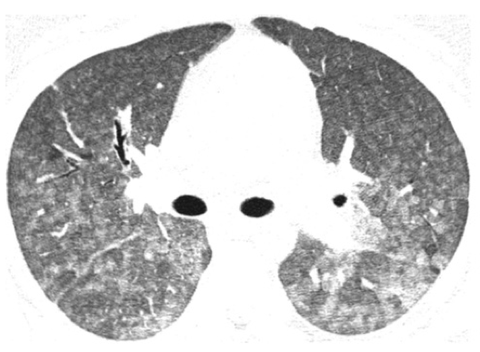

Diagnostic Tests

Several diagnostic tests may be employed to confirm hypersensitivity pneumonitis and assess the extent of lung involvement:

- Imaging studies:

- Chest X-ray

- High-resolution computed tomography (CT) scan

- Chest X-ray and computed tomography (CT) scan. These scans may be able to show early signs of the disease and identify any scars on your lungs.